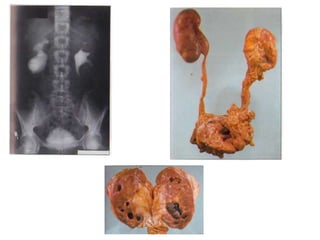

 Gross changes within urinary tract similarly depend on

duration, degree & level of obstruction

 Within intrarenal collecting system, degree of dilation is

limited by surrounding renal parenchyma

 Grossly, acutely hydronephrotic system can be associated

with little anatomic disturbance to renal parenchyma

 Chronically dilated system may be associated with

compression of papillae, thinning of parenchyma around

calyces & coalescence of septa between calyces

 Cortical atrophy progresses to point at which only a thin rim

of parenchyma is present

• Definition of GH: Adult renal pelvis containing 1 litre of urine or

1.6% of body weight

• Crooks et al. has given radiographic criteria: 1) Kidney occupies

hemi-abdomen 2) Meets or crosses midline & 3) about 5

vertebral bodies in length

• Seen more often in males than in females (2.4:1)

• > 500 cases of GH have been reported in literature

• GH usually presents: Asymptomatic enlargement of abdomen

noticed by patient or incidentally by his physician